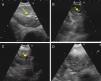

Hyperechogenic density in the interior of the LN (Figs. 1 and 2).

Fig. 2.Series of EBUS images of the mediastinal lymph node showing the different criteria (continued). (A) Presence of central hilar structure (arrow) in reactive lymph node. (B and C) Presence of central hilar structure with blood vessel (arrow) in another reactive lymph node; demonstration in Doppler mode in (C). (D) Indistinct margin with heterogeneous echogenicity in extrathoracic metastasis with the absence of central hilar structure.